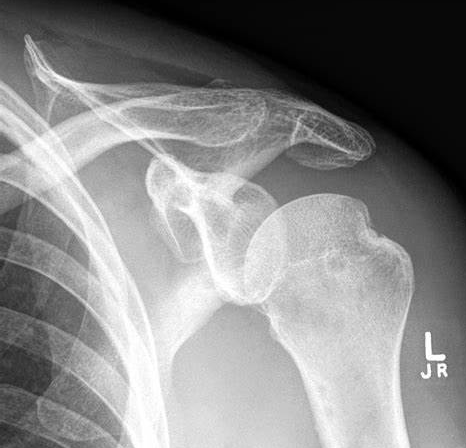

What fractures can occur alongside shoulder dislocations?

A

Humeral head

Greater tuberosity of the humerus

Acromion

Clavicle

(rotator cuff tears may also occur)

What do these X-rays show?